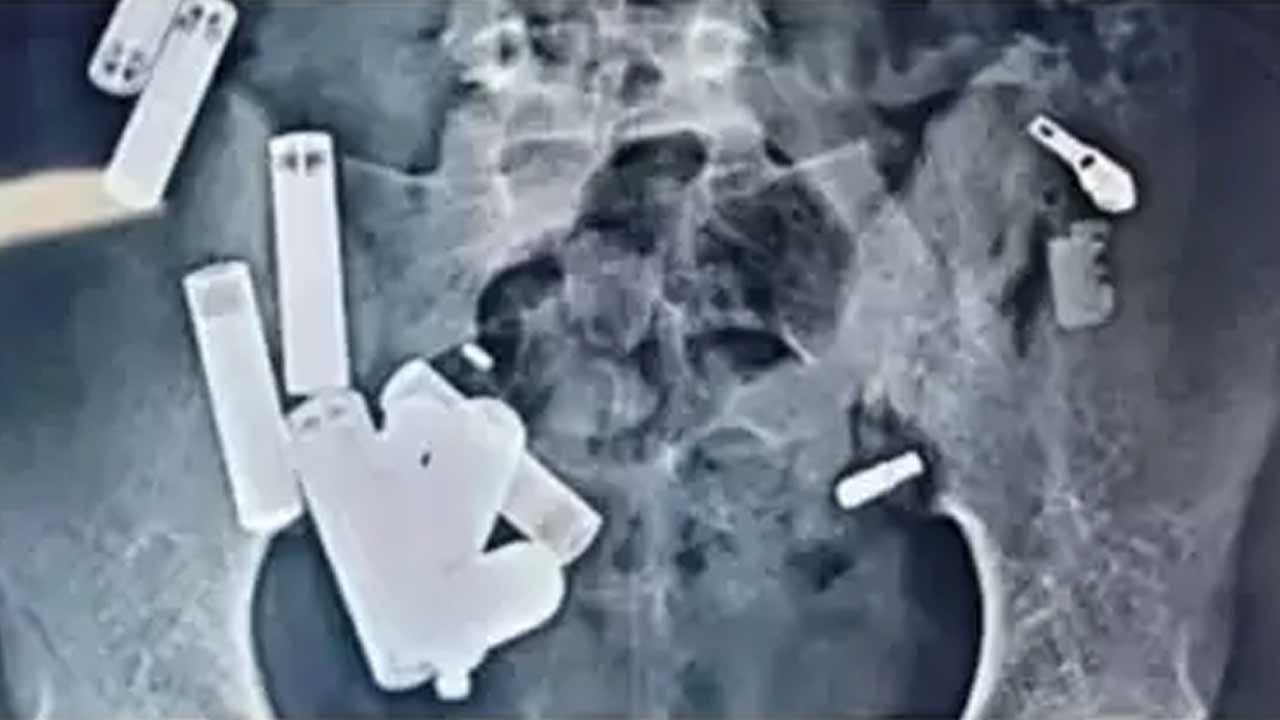

శస్తచ్రికిత్సల్లో ఎంత పురోగతి సాధించినప్పటికీ కొన్ని ప్రత్యేక కేసులు వైద్యులకు పెద్ద సవాళ్లను విసురుతుంటాయి. అలాంటి ఓ సవాలును ఏఐజీ హాస్పిటల్స్ వైద్యులు విజయవంతంగా అధిగమించారు.